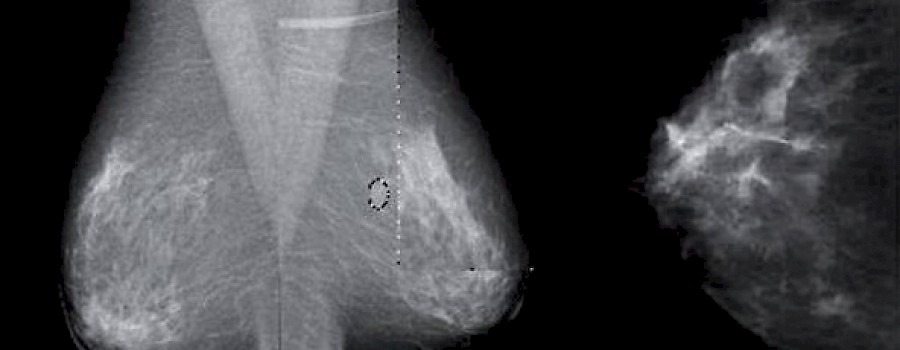

400 Fachleute für Brustkrebs diskutierten in Frankfurt am Main über Diagnosestandards für Brustkrebs in der Magnetresonanztomografie (MRT).